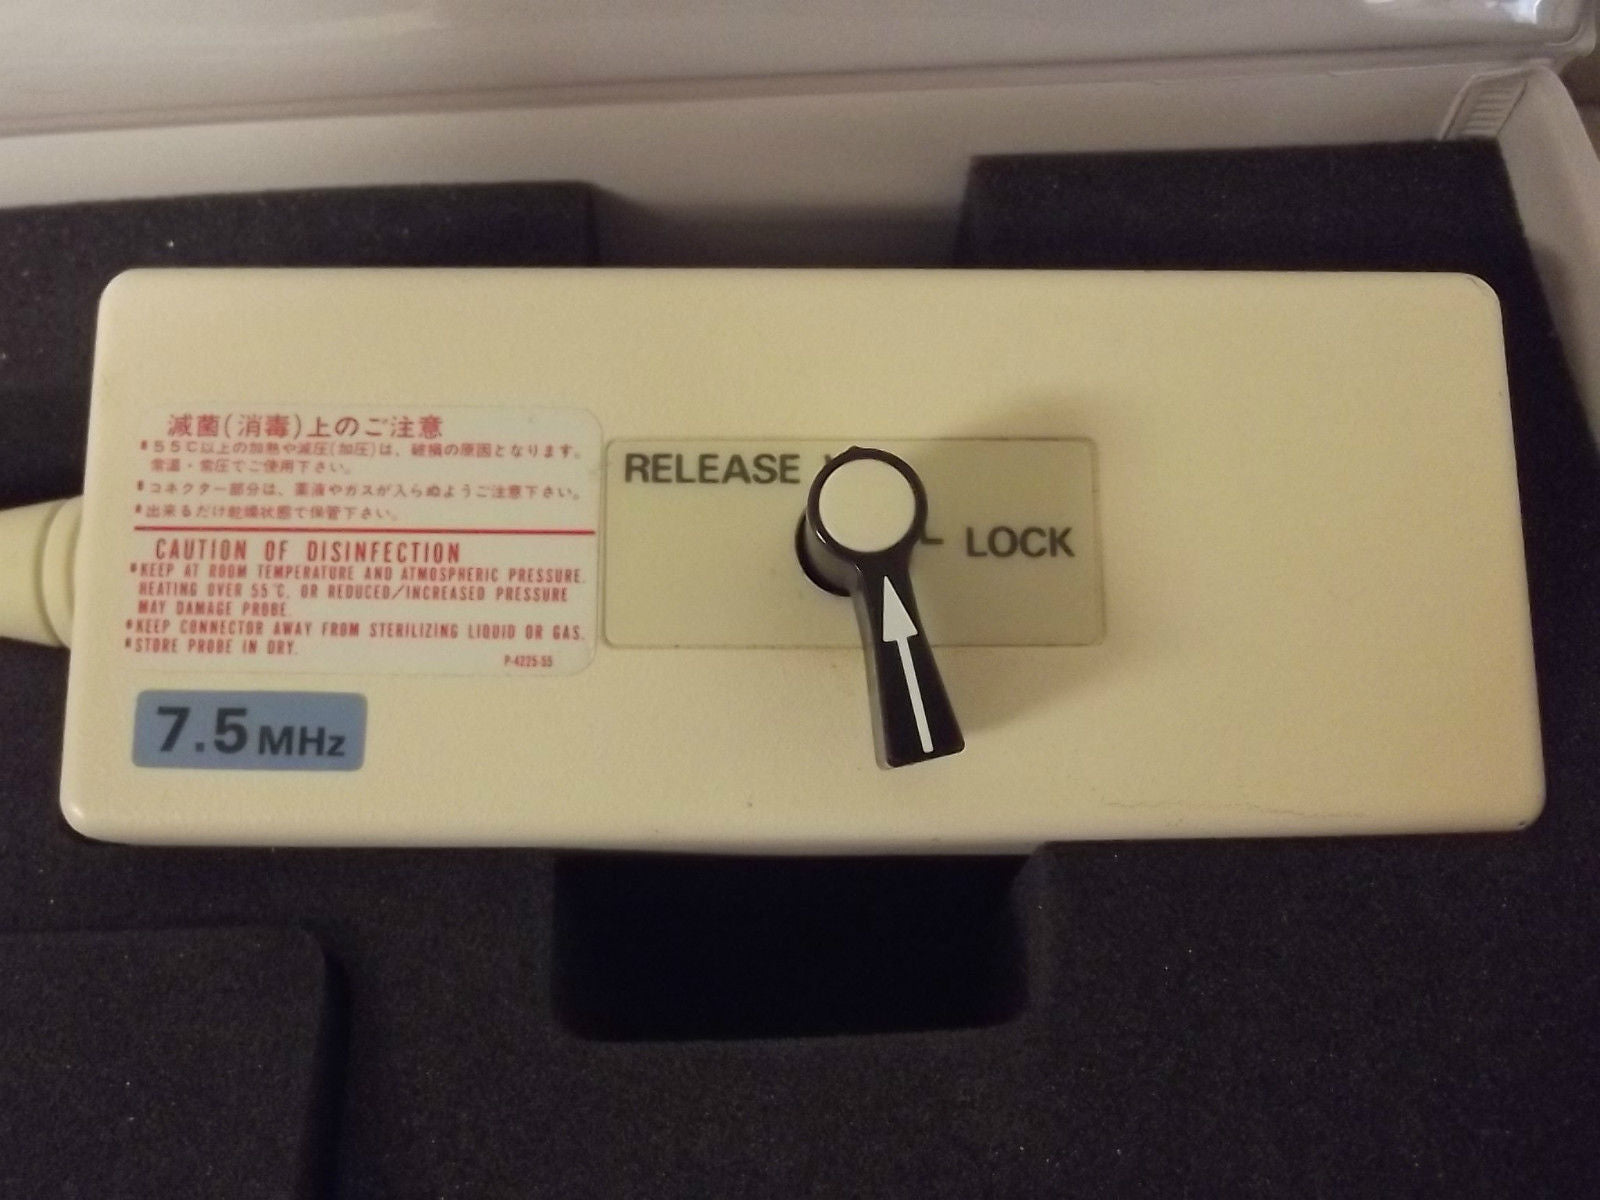

Aloka Ultrasound Probe Model: UST-959-3.5

Aloka Ultrasound Probe Model UST-SSD830P2-5